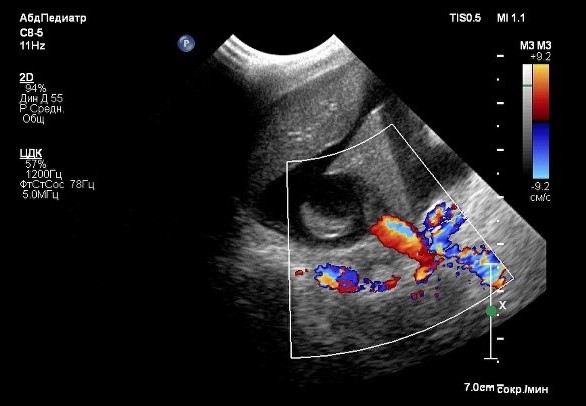

В ходе проведения УЗИ выявлена отрицательная динамика в отношении количества свободной жидкости в брюшной полости (до 6 см на просвет). Также обнаружены увеличение отека паренхимы поджелудочной железы, характеризующееся появлением признаков, известных как «тигровая поджелудочная железа», и нефролитиаз (фото 4). Данные изменения свидетельствуют о развитии тяжелой портальной гипертензии, что требует проведения незамедлительной диагностики для установления причин и разработки плана лечения.